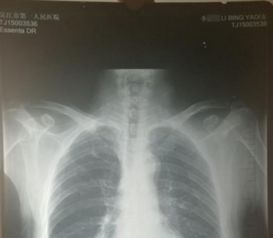

1、定期体检:定期进行全面的体检,包括血液检查、影像学检查等,以便及时发现潜在的疾病风险。